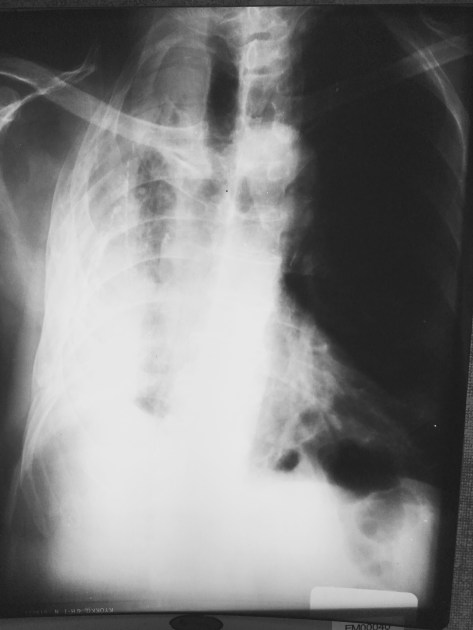

This nice 76 year old fellow told me that when he was 25 yrs old he ‘vomited up his lung.’ Well, he is correct that he doesn’t have a lung on the right side. However, I decided not to point out to him that it’s not anatomically possible to puke up your lung. Unless you ate it first…